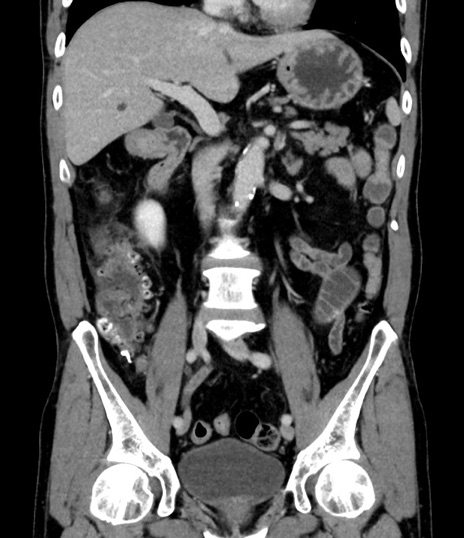

症例8(冠状断像)

【症例】 60歳代男性

【主訴】 黒色吐物

【現病歴】 4日前から嘔気自覚、2日前の朝食後にも嘔気あり、自分で手で嘔吐反射起こし嘔吐したところ血が混ざっていたため受診。

【既往歴】 5年前汎発性腹膜炎を伴う急性虫垂炎で手術、高血圧、前立腺肥大症、高脂血症

【身体所見】 腹部正中に手術癩痕あり 腹部平坦・軟圧痛なし膨満感あり

【データ】WBC 8400、CRP 4.54